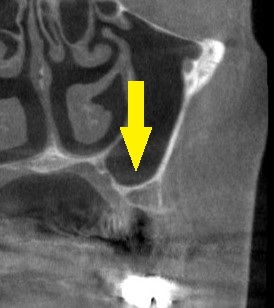

レントゲン、CTを撮影してみると、上顎の臼歯部ではよくあることですが、骨がやや薄く骨造成なしでインプラント埋入は困難でした。

下の写真2段目が術前のCT、やや骨が薄いのが分かります。